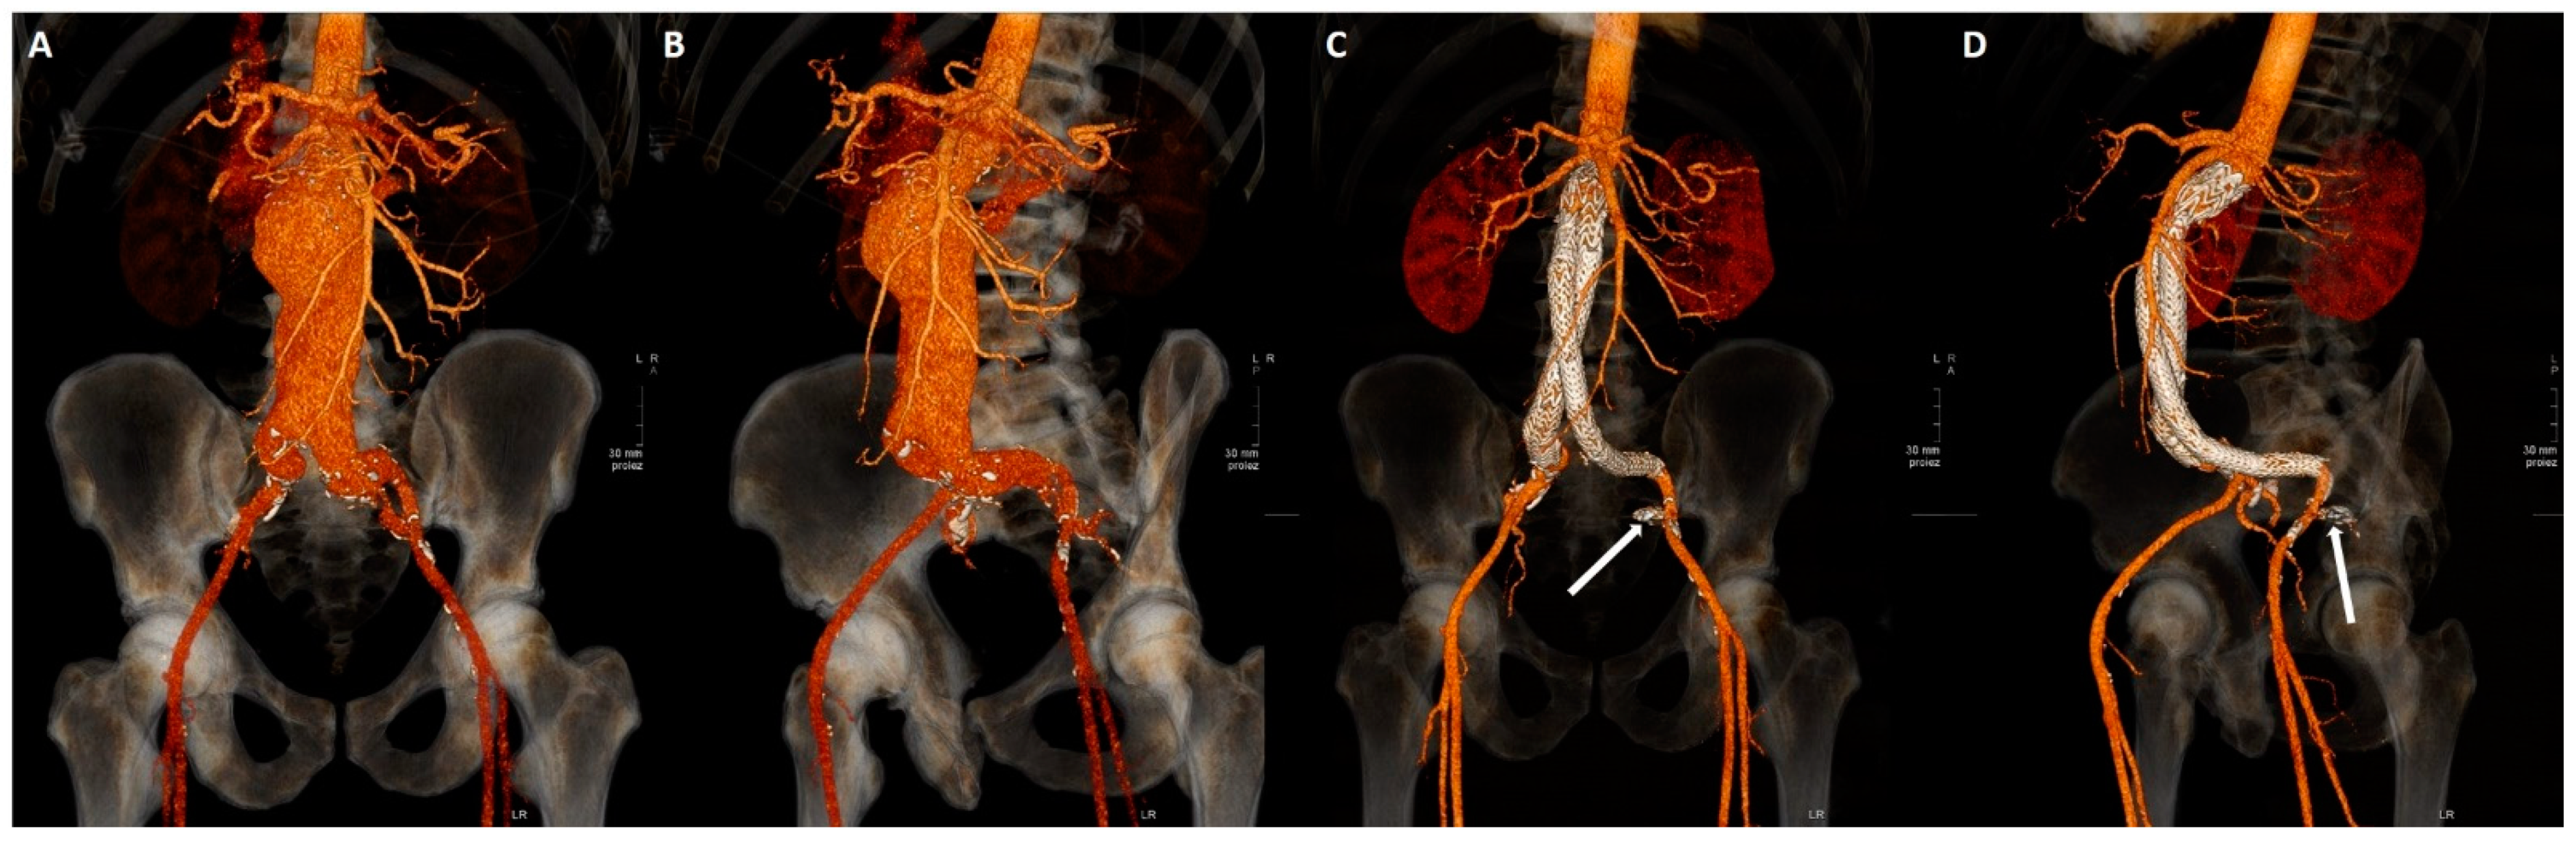

2.3. Embolization Technique